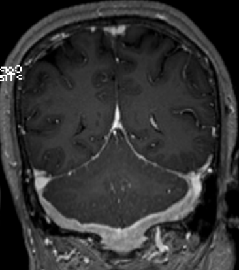

2013-8-2 MRI

2013-8-2 CT

腰穿脑压240